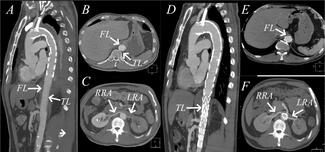

Jingjing Chen, MD; Li Zhu, MD

A 55-year-old man with Stanford type B aortic dissection underwent thoracic aortic and left common carotid artery mulched stent implantation. He was admitted to our hospital after surgery with low urine output, and it was suspected that the...